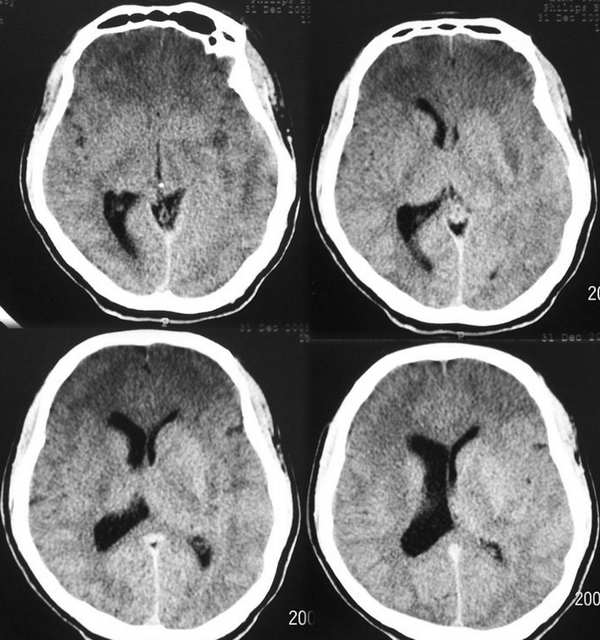

患者 m 45 头痛 言语不清一周

上面的ct是平扫

左侧基底节额颞叶稍长t1长t2信号,增强见边缘与脑回样强化,作侧脑室变窄。ct平扫呈等与扫地密度以等密度为主。考虑1脑炎。2脑肿瘤[淋巴瘤]

1、占位效应明显,支持肿瘤 2、额叶低密度,支持缺血性改变

ct示左颞叶等,略低密度影,mr示左额颞叶t1wi呈低信号,t2wi呈高信号,增强后边缘不均匀强化,左侧脑体部明显受压,考虑脑梗塞可能性大

首先考虑脑梗塞,肿瘤mri表现多为长t2信号,增强后多有明显的不均匀强化,本病例占位征象明显,如果是肿瘤恶性度是偏高的,增强后应该有明显的强化表现。临床病史比较短暂,增强后强化呈条片状,梗塞在三天为水肿高峰,占位明显。综合考虑脑梗塞可能性大。

mr 片与ct 吻合不起来。ct上双侧额叶大片低密度影像,而mr上额叶却没有异常信号。是不是两个检查相隔时间较长?或者ct 扫描时头颅不在机架中心而偏下出现的伪影?如果不是伪影怎么没有一点占位效应?

占位效应明显,支持肿瘤 2、额叶低密度,考虑脑梗